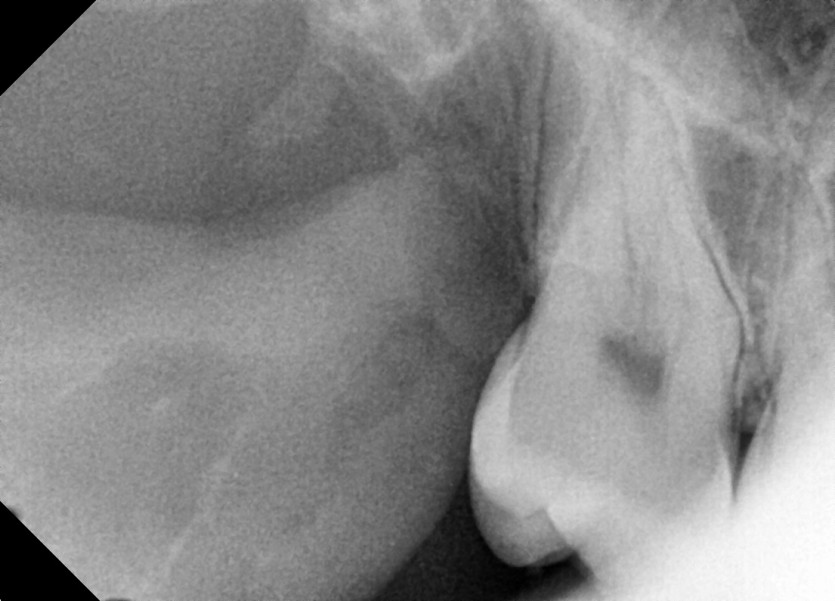

#18,48 사랑니 발치

구강외과 전문의가 당일 발치했습니다.